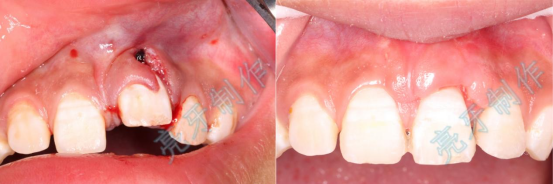

病例三:牙齿嵌入牙槽骨,松动明显,经过治疗,稳定了,也恢复了外形。

病例四:右侧前牙牙齿嵌入牙槽骨,无法咬合,治疗后,恢复功能和外形。